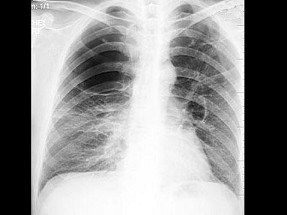

影像检查胸部X线检查可以了解肺癌的部位和大小,可看到由于支气管阻塞引起的局部肺气肿、肺不张或病灶邻近部位的浸润性病变或肺部炎变。

周围型肺癌